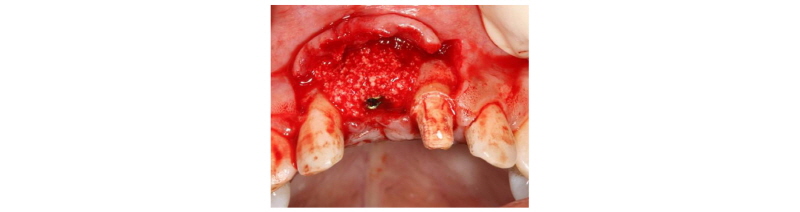

A 39-year-old male patient visited to the KyungHee University Dental Hospital with periapical abscess in the right maxillary central incisor. After clinical and radiographic examination, the tooth was planned to be extracted. The patient didn’t want to prepare the additional adjacent teeth. The right maxillary central incisor was planned to restore implant restoration and the left maxillary central incisor decided to proceed re-endodontic treatment and crown restoration (Fig. 1). Because of relatively young age of the patient, there was a lot of interest in esthetic results. Therefore, we planned to make provisional implant restoration and make a definitive prosthesis duplicating the emergence profile of the provisional restoration, and planned to use zirconia abutment when restoring the definitive prosthesis. First, preparation of maxillary left central incisor was done and maxillary right central incisor was extracted and cantilever provisional restoration was restored (Fig. 2, 3). Re-endodontic treatment of maxillary left central incisor was also progressed. After 3 months healing periods, implant placement was planned under evaluation of cone beam computed tomography scan with radiographic stent (Fig. 4). Implant placement was guided by surgical stent with bone graft (Bio-oss, Geistlich Pharma AG, Wolhusen, Switzerland) (Fig. 5, 6) and there were no systemic diseases would become problematic for implant surgery. Clinical and radiographic evaluation neither described any obvious active infection. Internal submerged type implant (4.0 mm×12.0 mm Implantium, Dentium, Korea) was placed and healing abutment was tightened. After surgery, provisional restoration was modified (Fig. 7). 3 months after implant surgery, fixture level impression was taken using pick-up impression coping (DPU 40 15 HL, Dentium, Korea) for provisional restoration (Fig. 8). Then, provisional crown with plastic provisional abutment (RAB 45 20 PHL, Dentium, Korea) was set for gingival molding (Fig. 9). During 3 weeks of provisional restoration period, the patient was satisfied with the function and the appearance of the provisional restoration. To transfer the emergence profile of provisional restoration, transfer technique was used with polyvinyl-siloxane impression material (Silagum, light body and putty, GmbH, Germany) (Fig. 10) and impression coping was modified. The final fixture level impression was taken using polyvinyl-siloxane impression material (Express light body and regular body, 3M ESPE, St Paul, MN, USA) after connection of modified pick-up impression coping (Fig. 11). A CAD/CAM zirconia abutment was milled and abutment adapted. Resin material (Pattern Resin LS; GC, America) and wooden sticks were used for delivery to laboratory of anterior teeth horizontal line. Midline also marked (Fig. 12). Splinted porcelain fused to zirconia prosthesis was fabricated. The root of the maxillary left central incisor being short and the prognosis being poor, so the crown was splinted with the maxillary right maxillary incisor implant prosthesis. The definitive crown and abutment were delivered to patient (Fig. 13). The esthetic, marginal fit was evaluated and the zirconia abutment was tightened to 30 Ncm using torque controller and splinted maxillary right and left definitive prostheses was set final cementation with resin-modified glass ionomer cement (FujiCEMTM, GC, Japan). Within the 3 years follow-up after treatment, the patient satisfied with the functional and esthetic outcomes, and the gingival architecture preserved that form.

Fig. 5. Implant placement using surgical guide. |

Fig. 6. Bone graft after implant placement. |